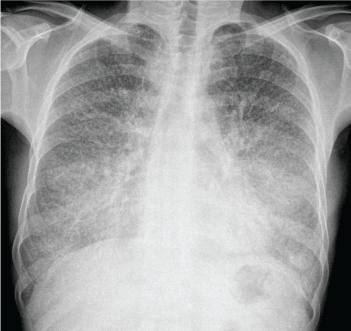

A 51-year-old non-smoking man, refered to our pulmonary medicine clinic with a 3 years history of severe shortness of breath. His complaints has increased even more in the last 1 year. There was no history of fever, weight loss, hemoptysis and old cronic infections like tuberculosis. Physical examination appeared bibasilar crackles. The pulmonary function test showed subtle restrictive findings and there was no pathologic findings on the blood examination. Chest X-ray (Figure 1) showed, dense, numerous, bilateral diffuse micronodular opacities predominantly lower zone. Computed Tomography (CT) of the chest (Figure 2) showed symmetrical lower lobe predominant widespread nodular intra-alveolar opacities of calsific density. Also there was diffuse septal thickening (because of calcification) and diffuse ground-glass attenuation (crazy paving pattern) and subpleural multiple small cysts (black pleura sign). Transbronchial biopsy was performed, confirming the diagnosis of Pulmoner Alveolar Microlithiasis (PAM).

Figure 1: Chest radiogrph shows fine, diffuse, symmetric, dense micronodular (sand strom sign) especially in the basal region.